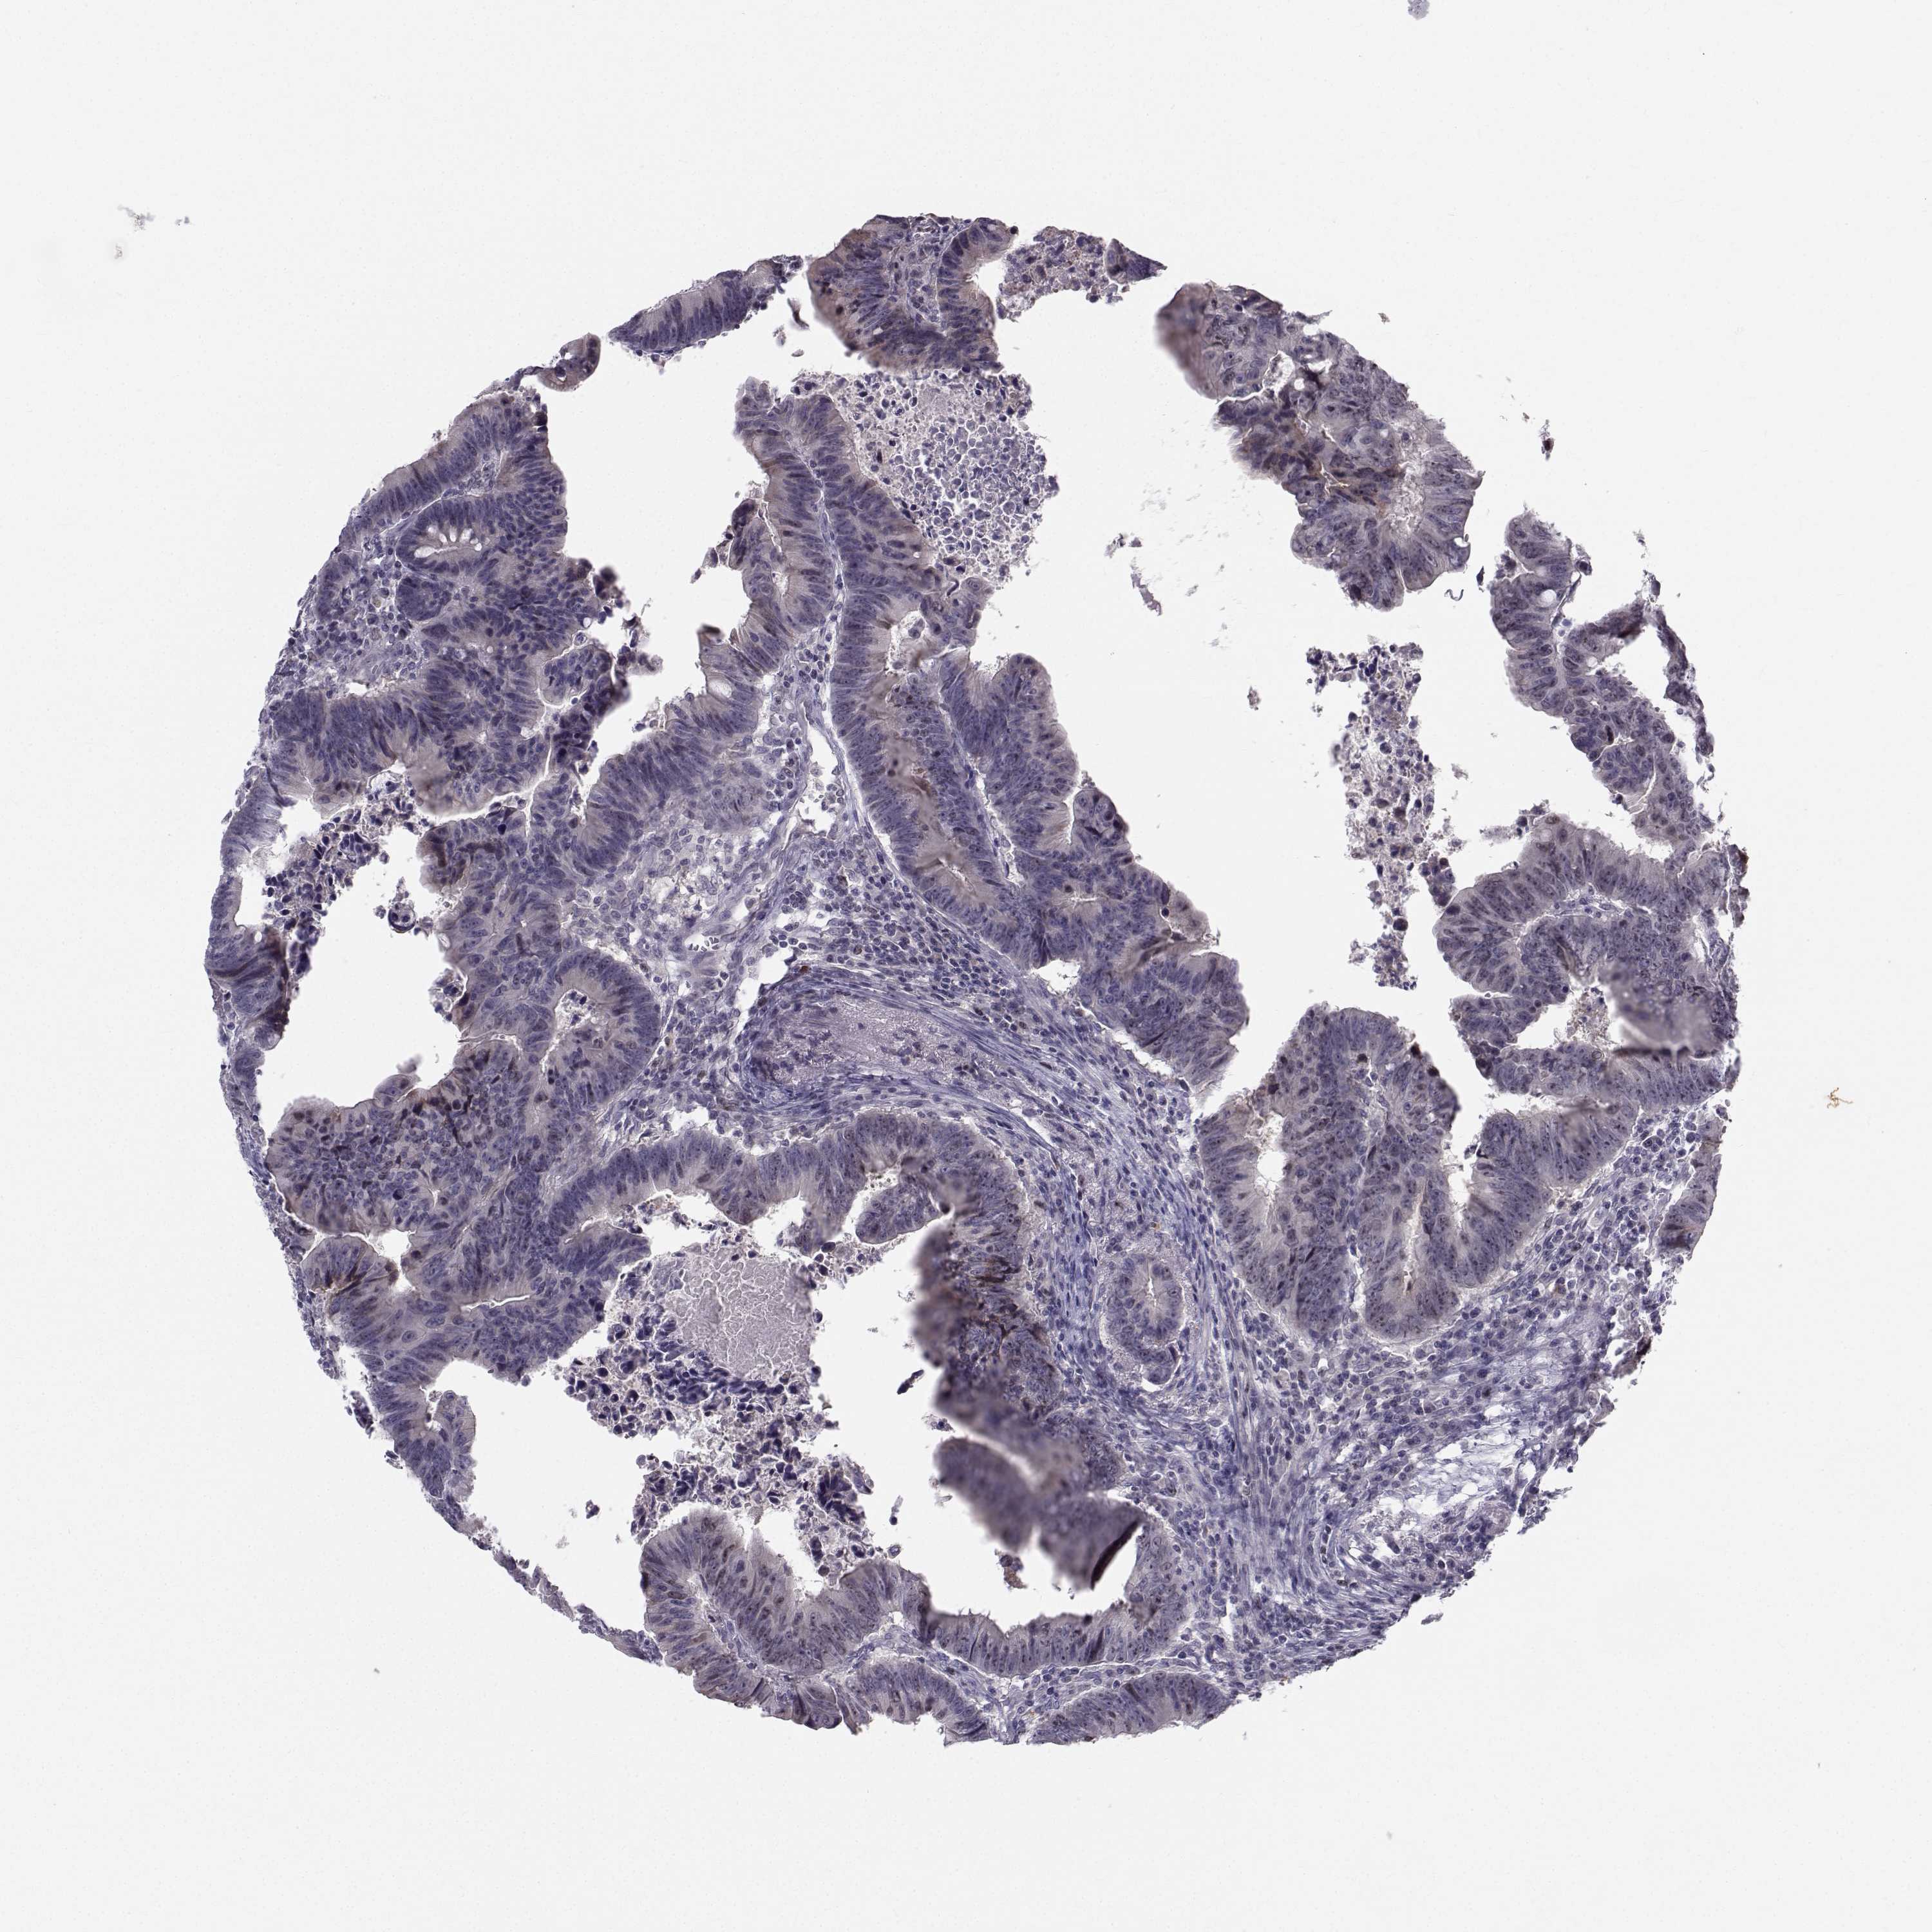

CANCER COLORECTAL CANCER Show tissue menu

Colorectal cancer

Human cancer

Colon adenocarcinoma